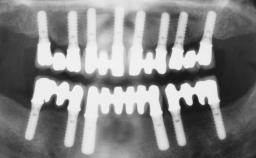

A fully edentulous 65-year-old woman was referred to our clinic for esthetic and functional dental rehabilitation. The patient presented with inadequate complete maxillary and mandibular prostheses, insufficient vertical dimension, and extensive tooth wear. The clinical examination and anamnesis showed no local or systemic contraindications, no signs or symptoms of bruxism, and an absence of smoking habits. The treatment proposed was implant placement in the mandibular interforaminal area and immediate loading with a fixed definitive prosthesis. A removable mucosa-supported complete prosthesis was indicated for the upper jaw, since its bone structure offered satisfactory retention and the financial condition of the patient disfavored a full-mouth implant-supported rehabilitation.

# of Implants 4